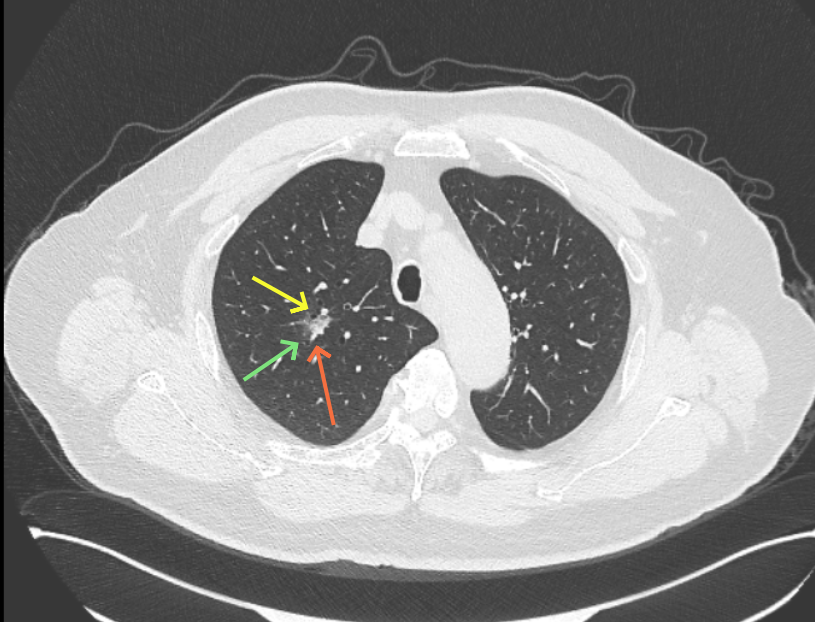

第三次问诊:2026.3

影像展示与分析:

但病灶B却显然进展!变成以实性成分为主的了!

我的意见:

两处均有进展,混合密度这处更显著些。那要考虑手术了的。之前也有碰到较短时间内进展是伴炎症或纤维增生的,但我们不能赌。建议手术为宜。意见供参考!

再看病灶B的2026年3月细节影像特征:

边缘位置也是较淡的磨玻璃成分。

上图是混合密度,轮廓较清,瘤肺边界欠清晰。

病灶A以及他处磨玻璃结节其实进展都是不明显的,略与2022年比,病灶A稍显明显点。病灶B开始时极淡,之前进展虽有但也甚微,直到2025年9月仍是磨玻璃成分为主,只是点状少许密度稍高成分。但在最近半年内却显然进展!若从影像上判断,基本上就得是浸润性腺癌了。那有几点:一是必不能再随访;二是大小来看仍是1A期;三是从快速进展来说,可能含有部分高危亚型,比如微乳头或实体型等;四是他处的磨玻璃结节以及病灶A显然不能用病灶B的转移来解释,仍考虑是多原发早期肺癌。

结友问能否先穿刺?我是这么考虑的:你这个病灶B一是位置深,且靠近附近的血管,不容易穿刺;二是从影像变化来看,基本上肯定是恶性的,不是100%,也是95%以上的概率。刚才我又在重建看冠状位与矢状位以及各次影像,目前混合密度的其实是后来者居上,原来刚开始是它比旁边的病灶密度淡的,但它的密度不是太纯,前次你自己也说似乎有点状偏实性成分。只是最近这半年进展特别快。这说明它的恶性程度较它边上原来就比较明显的那处恶性程度高,亚型中大概率有低分化的成分。所以从目前的影像来看,要尽快手术,而且切肺叶更为稳妥些。